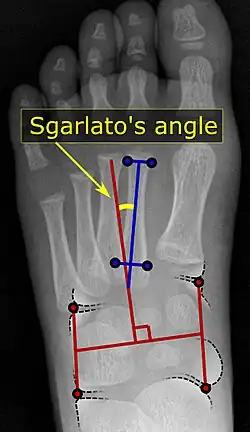

Pigeon toe can be diagnosed by physical examination alone.[10] This can classify the deformity into "flexible", when the foot can be straightened by hand, or otherwise "nonflexible".[10] Still, X-rays are often done in the case of nonflexible pigeon toe.[10] On X-ray, the severity of the condition can be measured with a "metatarsus adductus angle", which is the angle between the directions of the metatarsal bones, as compared to the lesser tarsus (the cuneiforms, the cuboid and the navicular bone).[11] Many variants of this measurement exist, but Sgarlato's angle has been found to at least have favorable correlation with other measurements.[12] Sgarlato's angle is defined as the angle between:[9][13]

- A line through the longitudinal axis of the second metatarsal bone.

- The longitudinal axis of the lesser tarsal bones. For this purpose, one line is drawn between the lateral limits of the fourth tarsometatarsal joint and the calcaneocuboid joint, and another line is drawn between the medial limits of the talonavicular joint and the 1st tarsometatarsal joint. The transverse axis is defined as going through the middle of those lines, and hence the longitudinal axis is perpendicular to this axis.

This angle is normally up to 15°, and an increased angle indicates pigeon toe.[9] Yet, it becomes more difficult to infer the locations of the joints in younger children due to incomplete ossification of the bones, especially when younger than 3–4 years.